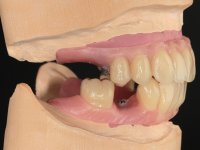

After the implant impressions with silicones, the working model was built with artificial gingiva. Then, the dental technician fabricates the record bases with the wax rims with the particularity of being screwed on the implants to achieve a proper stability. The correct vertical dimension and the lip support were determined with record bases screwed over the implants. To validate these records we have also used the “Individualized Geometric Analysis of Facial Harmony (AGIHF)” by Professor Carlos Silva.

Then, the teeth were mounted in the screwed record bases and function and aesthetics were clinically evaluated. After these evaluations, the dental technician develops silicone walls that guide the fabrication of the milled bars. The precise passive fit of the bars was checked clinically and with radiographs. Then, a pick-up impression with an individualized tray was done to achieve a functional impression of the soft-tissues.